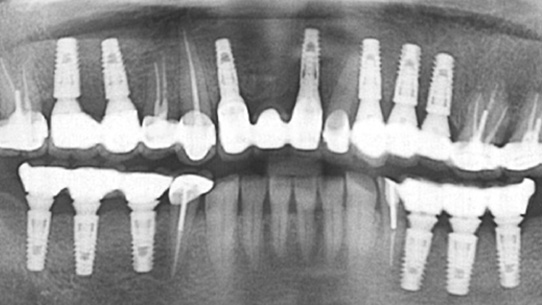

치아상실 상태가 오래 되어 적절한 영양섭취가 힘들어 “영양부족”으로 내원한 환자분. 우선 영양섭취를 위하여 음식물을 씹을 수 있는

임시치아를 빠르게 만들어 드렸습니다. 건강상태가 회복되어 상악은 12개의 임플란트를 식립 하고, 하악의 경우 잇몸 뼈가 많이 소실되어

2개의 임플란트를 식립하고 임플란트 틀니를 장착하였습니다.